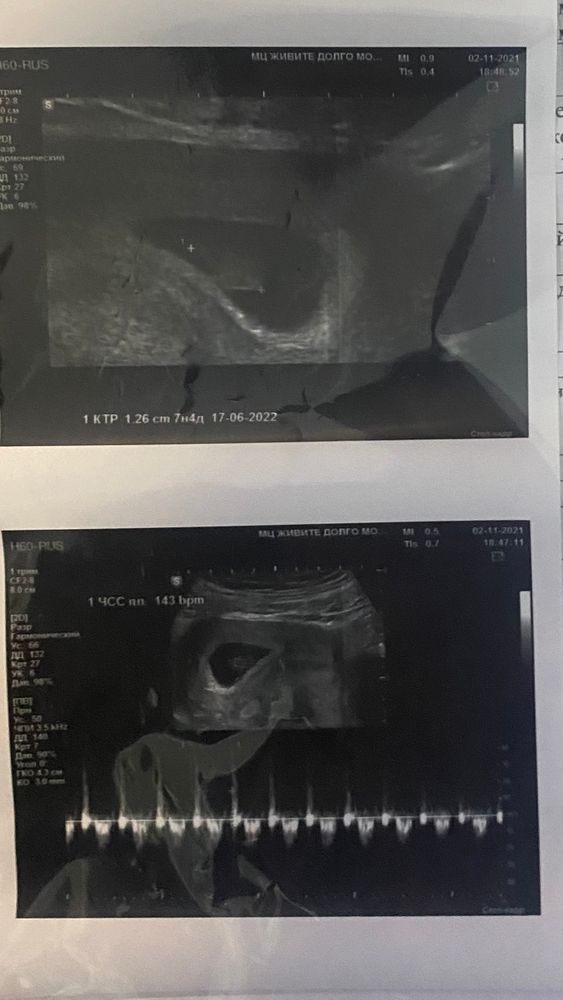

Всем привет ) я тут сходила на узи наконец-то послушала с/б успокоилась , правда врач сказала что у меня срок 7,4 а по месячным 8,2)))так боялась,а когда услышала с/б прям расплылась все в улыбке и глаза заслезились ☺️☺️☺️Вот решила с вами поделится